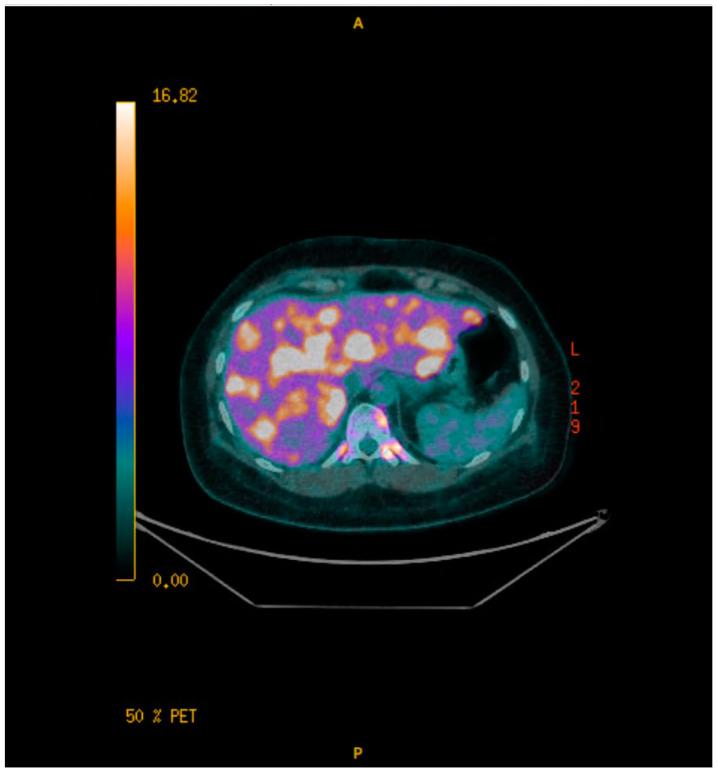

Ectopic adrenocorticotropic hormone syndrome (EAS) occurs when a tumor develops neuroendocrine differentiation with the secretion of ACTH resulting in hypercortisolism and possibly Cushing's syndrome (CS). Only 5-10% of CS cases are attributed to EAS; of these, breast tumors comprise less than 1%. Two known variants of breast neuroendocrine tumors include neuroendocrine-differentiated carcinoma and ductal carcinoma with neuroendocrine features. Currently, guidelines for treatment are limited and EAS is associated with significant morbidity and mortality. A 39-year-old female presented with a rapidly enlarging breast mass. Biopsy demonstrated invasive poorly differentiated breast carcinoma with high-grade neuroendocrine features and necrosis. Staging at diagnosis confirmed metastatic disease of the liver and bone. First-line chemotherapy (Cisplatin/Etoposide/Durvalumab) was initiated with evidence of disease progression after four cycles. Given a poor response to therapy, a simple mastectomy was performed for local control and complete pathologic analysis, demonstrating high-grade neuroendocrine carcinoma with large-cell features. Second-line therapy (Adriamycin/Cyclophosphamide) was initiated for three cycles after which the patient required admission for severe and refractory hypokalemia. Workup confirmed elevated ACTH consistent with paraneoplastic EAS and further evidence of disease progression. Third-line therapy (Nab-Paclitaxel) was initiated, and genetic testing was completed, confirming the PIK3 mutation, for which access to Alpelisib therapy was requested. Given symptoms of progressive severe CS with significant liver disease limiting medical therapies, the patient underwent urgent bilateral laparoscopic adrenalectomy after which she was able to be discharged home while awaiting additional systemic therapy. EAS resulting in CS secondary to breast neuroendocrine carcinoma is a rare and challenging diagnosis. Further research is needed to inform treatment guidelines to improve outcomes. While patient survival is dependent upon the underlying disease process, laparoscopic bilateral adrenalectomy is an accepted, definitive treatment option.